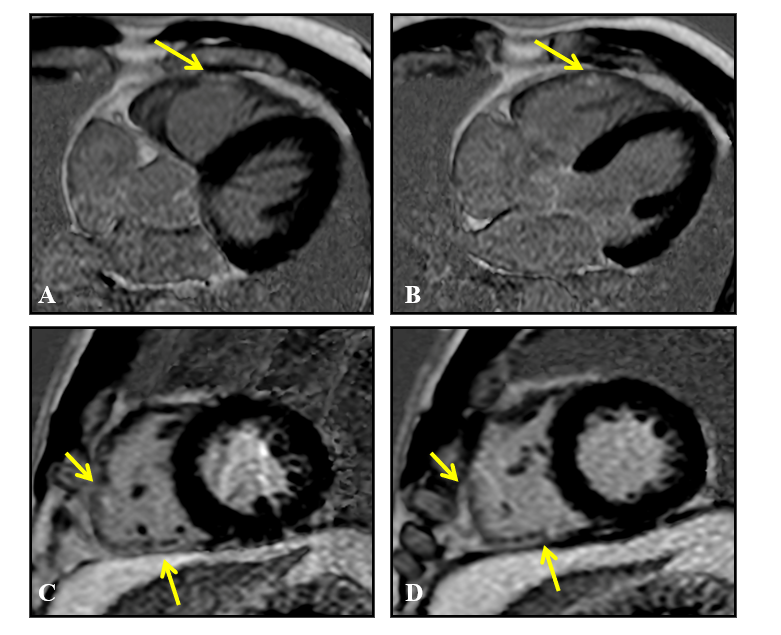

Figure 3 Magnetic resonance imaging, late gadolinium enhancement sequences, 4 chambers (A and B) and short axis (C and D) showing pathological late enhancement areas in the myocardium of the inferior and lateral segments of the right ventricular free wall (arrows), without associated left ventricular involvement.